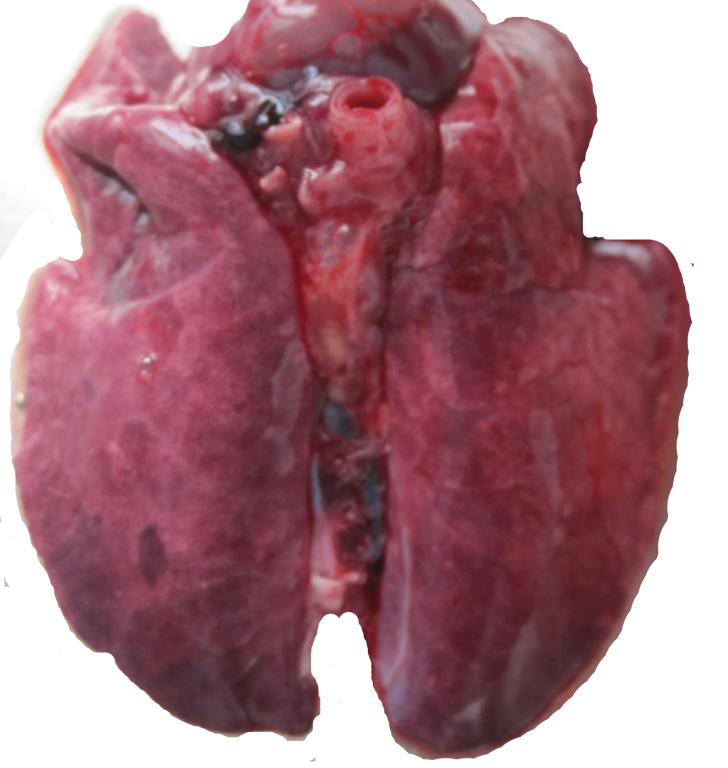

仔猪伪狂犬病解剖病变

肺淤血、水肿,重量增加

肺脏淤血、水肿